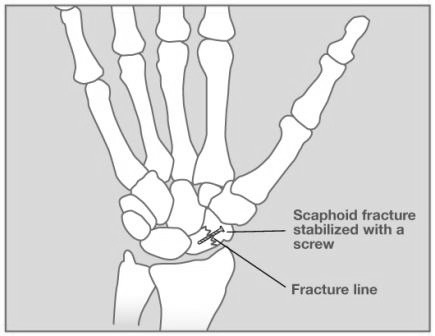

Scaphoid fractures need to be treated appropriately.  There are various treatments recommended depending on the type and severity of the scaphoid fracture.  This diagram shows a compression screw that has been placed across the scaphoid fracture site.